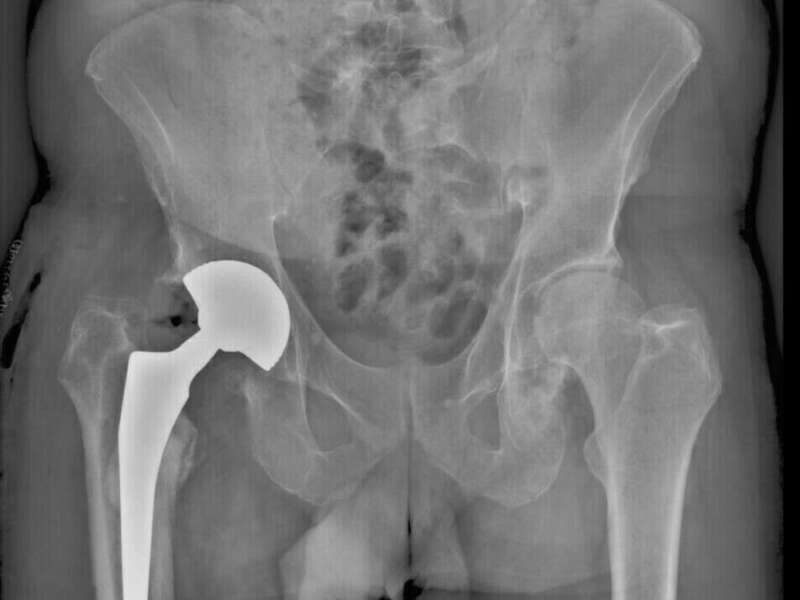

Le bilan radiologique (radiographies standards et scanner) recherche un liseré péri-prothétique correspondant à l’ostéolyse péri-prothétique voire même une migration des implants. Votre chirurgien étudiera l’ensemble de vos radiographies post-opératoire pour détecter l’apparition d’un liseré autour de la prothèse ou d’un déplacement des implants. Cependant, cet examen peut être normal.

Cas 2. Descellement de cotyle antéversé secondairement